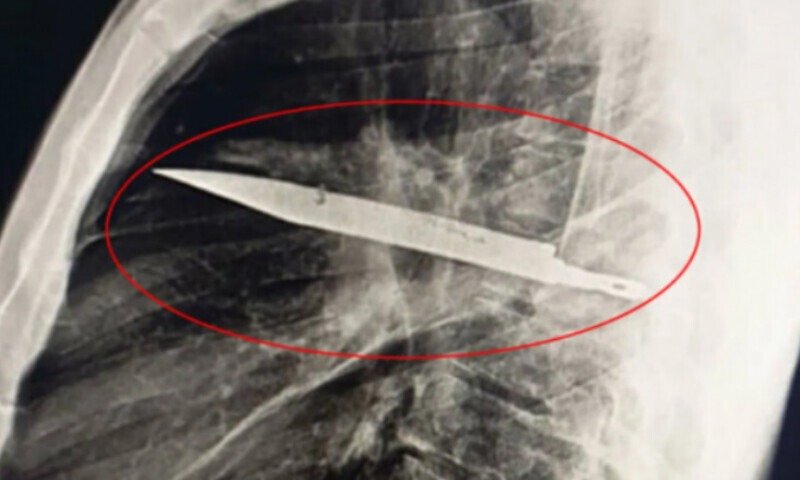

ڈاکٹروں نے اس کا ایکسرے کیا اور یہ حیران کن بات سامنے آئی کہ چاقو اس کے دائیں کندھے کی ہڈی میں داخل ہو کر سینے میں پھنسی ہوا تھا۔ خوش قسمتی سے، اس نے جسم کے اہم اعضا کو متاثر نہیں کیا تھا، لیکن اس کے اندر ایک لمبے عرصے سے انفیکشن موجود تھا۔

ڈاکٹروں نے اس بات پر حیرت کا اظہار کیا کہ یہ چاقو اس شخص کی زندگی کے لیے خطرہ بن سکتا تھا۔ خوش قسمتی سے، اس کے جسم نے اس غیر ملکی شے کو ایک فائبر کی کیپسول میں محفوظ کر لیا تھا، جس نے سوزش اور ٹشوز کو مزید نقصان سے بچایا۔ تاہم، اس حفاظتی ردعمل کے باعث چاقو کی موجودگی سے متعلق سنگین پیچیدگیاں چھپ کر رہ گئی تھیں۔